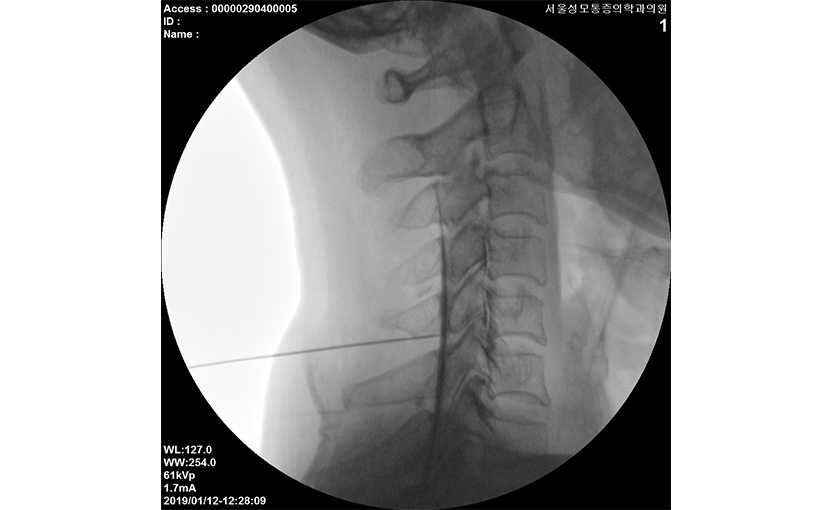

영상장치를 통해 신경 뿌리가 나오는 구멍이나 부종이 일어난 부위에 주사바늘을 넣은 후 국소마취제, 유착방지제, 스테로이드를 주입하는 치료입니다. 신경뿌리 주위의 유착과 압박 상태를 알 수 있기 때문에 진단과 동시에 치료가 가능하며 거의 모든 통증질환에 사용되는 광범위한 1차 치료법입니다.

본원에서는 실시간 x-ray를 이용한 정확한 치료가 가능한 두 개의 영상 치료실에서 환자에게 가장 효과적인 접근법을 사용한 약물의 주입을 시행하고 있습니다.